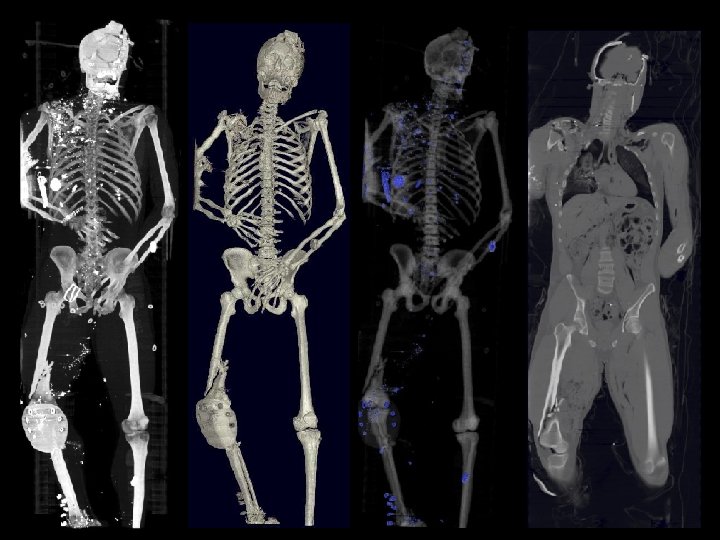

Information Representation of a Patient Medical equivalent of CAD/CAM Holomer Total body-scan for total knowledge Virtual Soldier Program Multi-modal total body scan on every trauma patient in 15 seconds Satava March, 2004

Information Representation of a Patient Medical equivalent of CAD/CAM Holomer Total body-scan for total knowledge Virtual Soldier Program Multi-modal total body scan on every trauma patient in 15 seconds Satava March, 2004